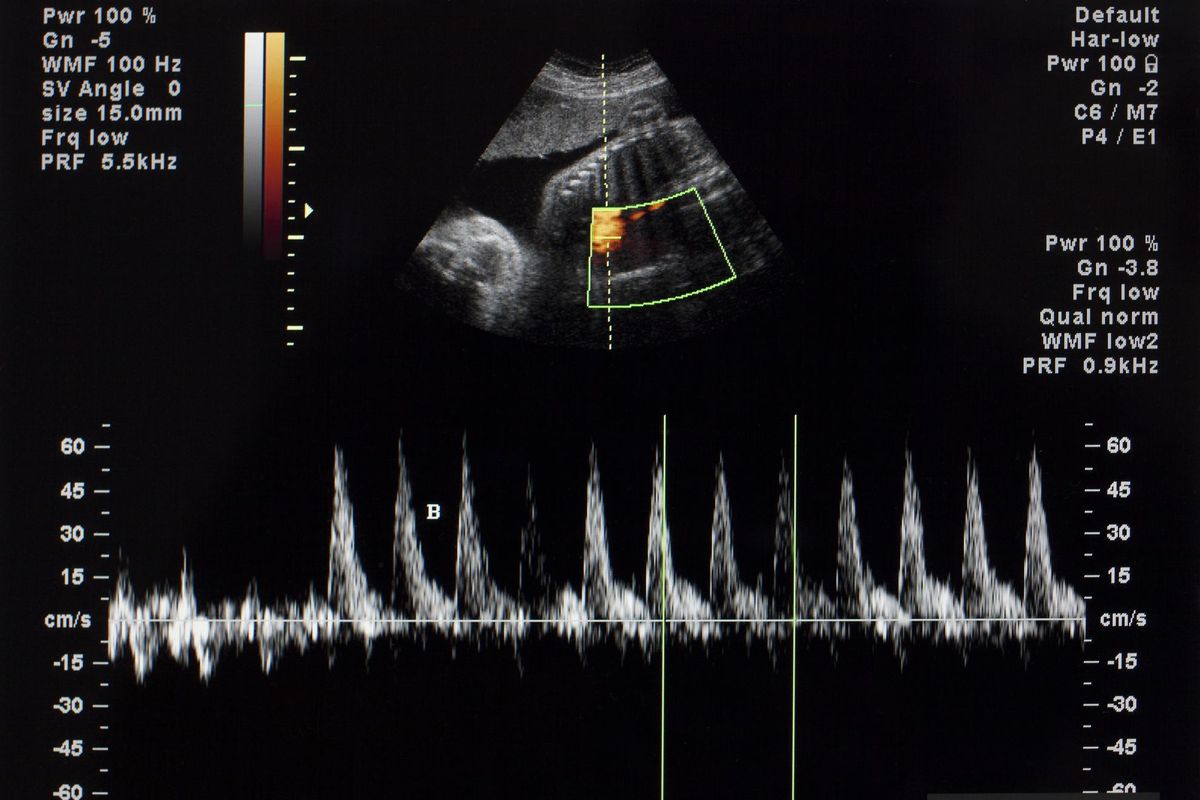

Va da sé che quelle informazioni devono essere massimamente chiare, semplici e veritiere. Ora, se una donna chiede di abortire non può non essere informata che la conseguenza sarà la morte del bimbo che porta in grembo: il suo cuoricino battente, si fermerà. Per sempre. È la terribile verità, che non ammette bugie. Perché, di bugie, su questo tema, se ne sono dette a vagonate, dal 1978 ad oggi: dal grumo di sangue, all’ammasso di cellule, al materiale biologico, allo scarto tissutale, ad un’appendice materna di cui disporre. No cari signori, nulla di tutto questo: è il cuore di un bimbo che si ferma e che l’intera società civile avrebbe il dovere assoluto di cercare di proteggere e far nascere, per rispetto a lui e alla mamma. Già, perché nessuna mamma vorrebbe eliminare il proprio piccolo e, quando lo fa, lo fa perché è sola, abbandonata, disperata, ricattata, senza nessuna concreta alternativa che aiuti lei e il suo bimbo a vivere. Questo è il vero tema da affrontare quando parliamo di aborto. Il resto è solo fuffa ideologica, inganno e mistificazione di chi ha paura della verità.

Faccio il neurochirurgo da oltre 40 anni, quando devo operare al cervello un paziente che a me si rivolge, ho il dovere assoluto di informarlo dettagliatamente di quanto potrà accadere: se c’è rischio di morte, ho il dovere di dirlo esplicitamente, correlando il tutto con dati e statistiche. E se non lo faccio, vengo meno a un dovere sia deontologico che legale, passibile di sanzione. Ora, far ascoltare il battito del cuoricino del bimbo prima della decisione abortiva definitiva ha certamente un grande impatto emotivo, ma è la pura e semplice verità, che non può essere ignorata, se vogliamo che la decisione finale sia veramente consapevole. Anche dire a una persona che domani dovrà essere operata, o sottoposta ad un pesante ciclo di chemioterapia, che rischia di morire, ha un impatto psicologico enorme… ma non si può e non si deve tacere! E così come facciamo in questi casi, in cui accompagniamo la scelta garantendo che «ce la metteremo tutta» per ottenere il meglio, perché non promettere a quella mamma che «ce la metteremo tutta» per garantire una vita buona a lei e al suo bimbo? Sono molti anni, che in ogni piazza, convegno, dibattito, conferenza vado ripetendo una domanda indirizzata alla ragione e al cuore di ogni cittadino: «Chi ci perde, in particolare nella nostra Italia, se riusciamo a far nascere un bimbo di più?».